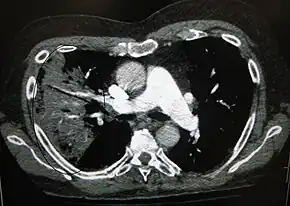

A CT scan can give additional information in indeterminate cases.[34] CT scans can also provide more details in those with an unclear chest radiograph (for example occult pneumonia in chronic obstructive pulmonary disease) and is able to exclude pulmonary embolism and fungal pneumonia and detecting lung abscess in those who are not responding to treatments.[33] However, CT scan is more expensive, has a higher dose of radiation, and cannot be done at bedside.[33]